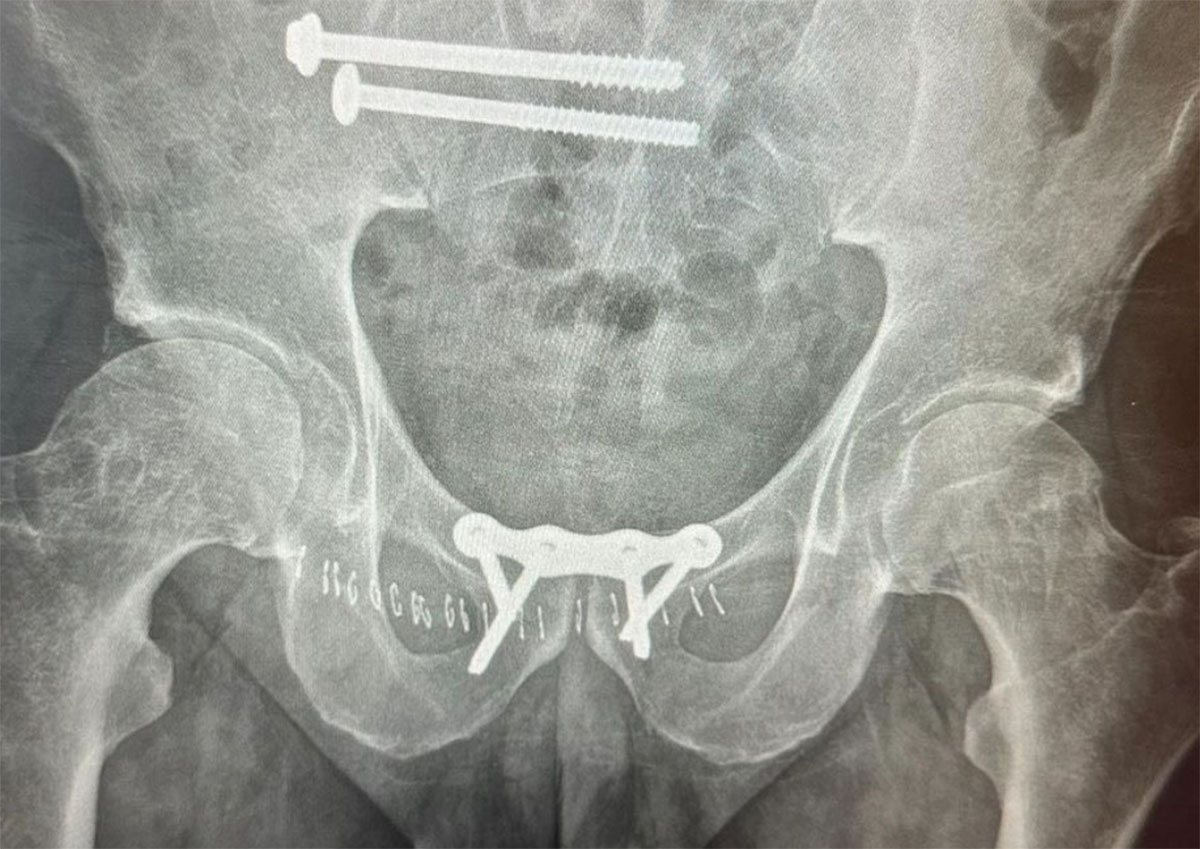

“Coco broke his pelvis and sacrum after getting caught inside by a cleanup set,” Greg Long explained in a crowdfunding campaign he started to help Nogales. “He was taken to the hospital in Ensenada where he stayed for almost two days before being told they would not operate on him and was asked to leave the hospital.”

Nogales went under the knife to pin his bones back together and all went well. Now, though, he’s looking down the barrel of months of painful rehab and a hefty hospital bill.